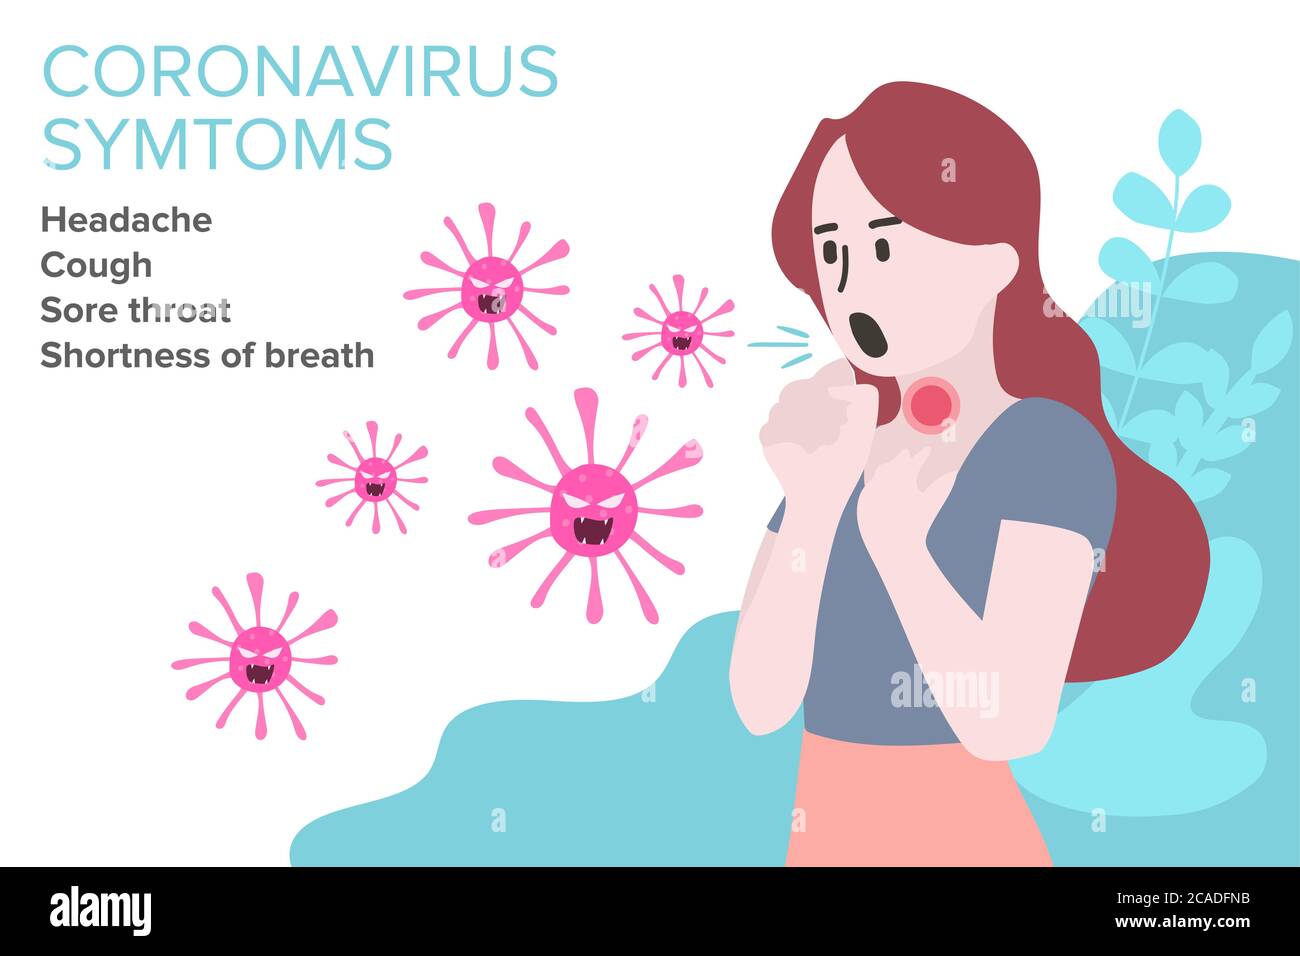

RF2CADFNB–Segno infografica con Cartoon ha tosse, febbre, Gola irritata e freddo in Coronavirus o Covid-19 focolaio.